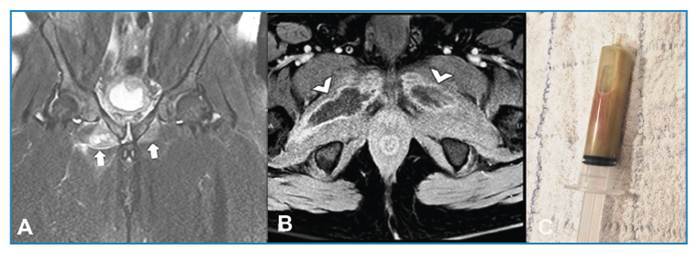

Pyomyositis in an immunocompetent man.